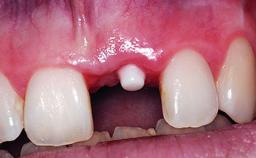

Replacement of an Upper Right Central Incisor with Root Resorption: Ridge Preservation, Delayed Placement of an NC Bone Level Roxolid Implant

A 32-year-old female Caucasian patient with a compromised maxillary right central incisor was referred to us by a general dentist. Her chief complaints were discomfort and mobility of tooth 11 with unsatisfactory esthetics due to discoloration. The patient reported a previous trauma, some years earlier, as the origin of pathology on the afflicted tooth. Anamnesis was negative for any other dental or periodontal pathology in the remaining dentition. The patient did not take any medication and reported to be a light smoker (5–10 cigs/day). She had high esthetic expectations of her treatment. The extraoral examination revealed a high smile line with full exposure of her maxillary teeth and surrounding soft tissue in the area between the second premolars.

Bone Augmentation Horizontal|Simultaneous|Staged

Soft Tissue Grafting Staged